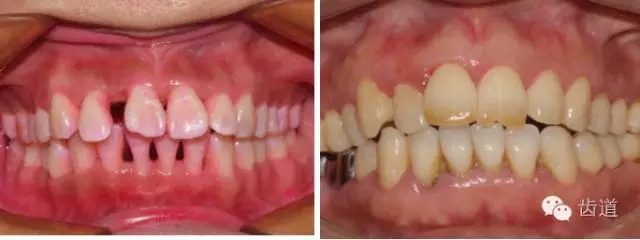

2、牙齦

(顏色、形狀、質(zhì)地、退縮、BOP、PD、附著齦)